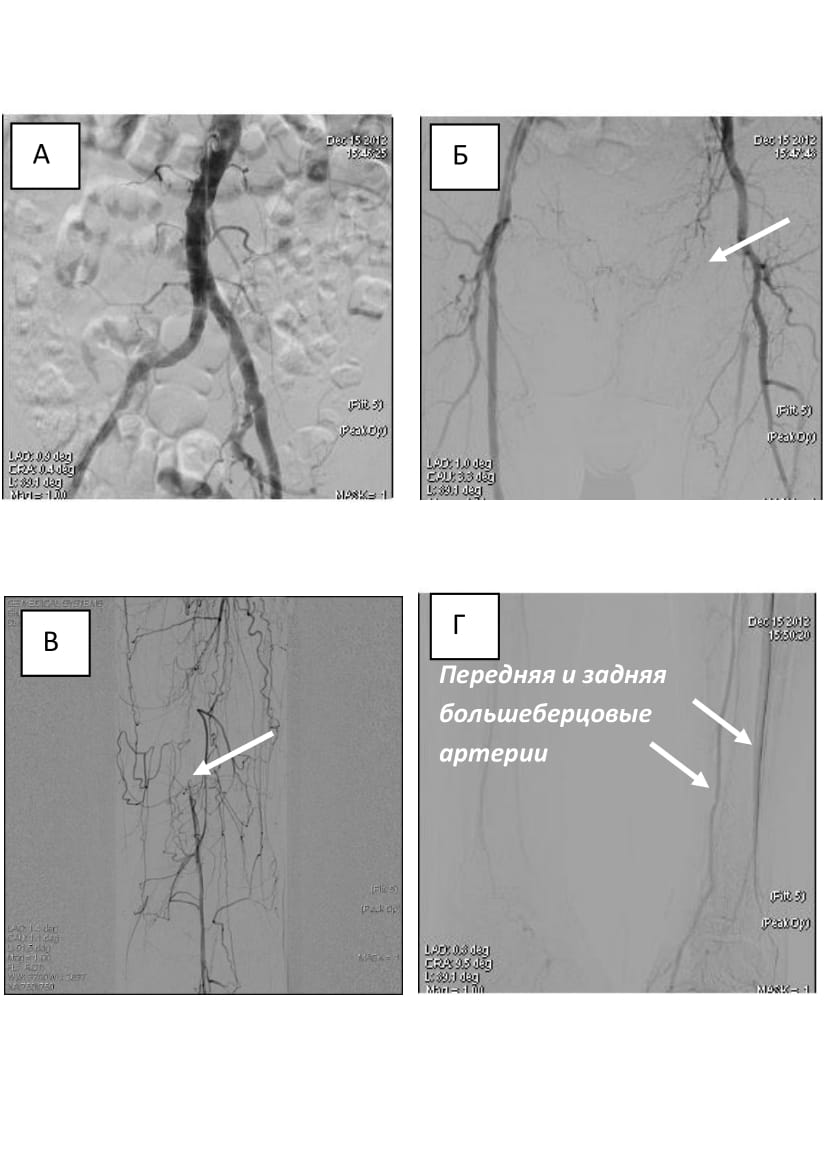

主动脉造影显示腹股沟下段动脉粥样硬化性改变。股总动脉不明显狭窄达30%,可见股浅动脉口至腘动脉闭塞,腘动脉闭塞,腘动脉第二段严重狭窄。显示了明显(60%)胫骨后动脉狭窄。

小腿动脉狭窄。保留了足底动脉弓(图5)。

图5。70岁M.病人的血管造影片:A—主动脉髂节,血流动力学无明显狭窄;B—股浅动脉闭塞(箭头所示);C—腘动脉血流动力学明显狭窄(箭头所指);D—下肢动脉(箭头所示),远端外周阻力估计为3点